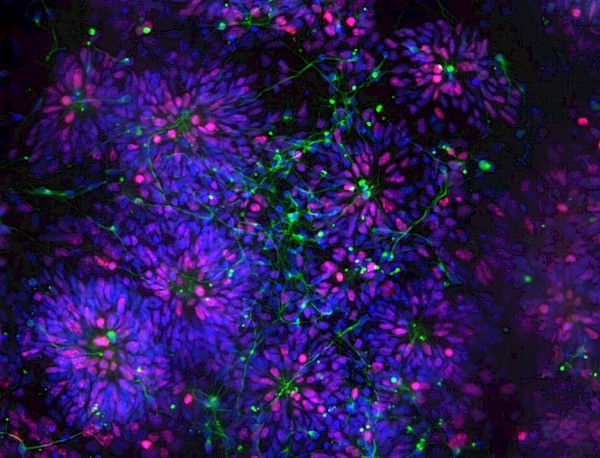

Normal? Festival of the Brain brings science and art together over four days to wonder at the brain. This year we are exploring neuroplasticity and asking what happens when we change our habits and behaviours - either through circumstance or conscious decision. Co-curated by Living Words, Folkestone Quarterhouse and Folkestone Fringe with input from the local community, we’ve been exploring empathy, self-help, laughter and awkward dancing to ask can you teach an old dog new tricks?